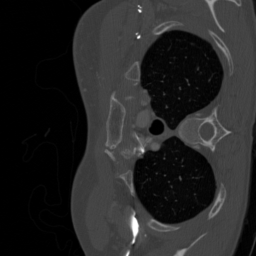

Computerized tomography

We consider parallel beam X-ray computerized tomography. It consists in probing line integrals of an object along a set of parallel lines that may be rotated and shifted. In this application the parameter represents the angles and shift at origin of the lines. The problem becomes blind if the object to image moves during the scan.

We trained the network using iterations using the ImageNet database. We initially used the Lung Image Database Consortium [7] database, but realized that it contains many improper slices (high noise, streaking artifacts, little contents…). We evaluated the algorithm on a curated version called LoPoDaP [58], containing less artifacts. The test dataset contains 4096 images.

As the blind inverse problem (5) requires differentiating the operator with respect to its parameters , we cannot use standard GPU-based libraries to compute the Radon transform [76]. We thus resorted to an homemade implementation that relies on a NUFT through the Fourier slice theorem. In order to reduce the important numerical cost and energy consumption of the experiments with CT reconstruction, we downsized the images to .

6.3.2 Computerized tomography

In this application, a model mismatch might occur due to the motion of a patient in the scanner. Correcting this mismatch is essential. Not accounting for it, can result in severe artifacts including some details loss and blur as can be seen in Fig. 6.

To identify the forward model, we ran the Adam optimizer on the parameters for iterations. In this application, represents the angle of the parallel shots and their shift at origin. All the reconstruction methods are able to significantly reduce the model mismatch, passing from maximal angles shifts of 7 degrees to less that 1 degree. Similarly, the shifts at origin are reduced from more than a pixel to about pixel. The reconstruction performance is significantly improved after estimating the forward model with PSNR increases of dB and more. The neural network trained on a family provides the best reconstruction results on this example.

Similarly to blind MRI, Table 4 shows that the “deep unrolled prior” method consistently provides good estimates of the forward model and significantly improves the reconstruction quality for the CT experiments.